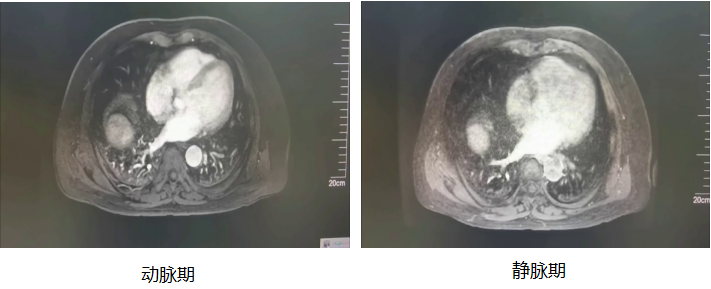

2021-04 肝脏增强MRI:

影像学表现:

肝脏形态欠规整,左右叶比例失调,肝左叶体积增大,肝裂增宽。肝实质信号不均,反相位信号减低。肝右叶见一肿块影,呈分叶状,其内多发结节融合,T2WI高信号、T1WI呈低信号、DWI呈高信号、ADC呈低信号。胆囊壁稍厚。左侧肾上腺增粗。脾脏体积增大。右侧腹腔内脂肪间隙略模糊。注入Gd-DTPA后,肝右叶肿块动脉期可见不均匀强化,内部见肿瘤供血血管,周围见多发结节状强化影,门脉期及延迟期强化减退,低于周围肝实质,边缘可见环形强化,肿块最大截面约98*94*99mm。门脉期可见门脉右支及主干、肠系膜上静脉充盈缺损。肝门区、胃底静脉迂曲增宽。

影像学诊断:

1.肝右叶占位,考虑肝癌可能,请结合临床;

2.门脉右支及主干、肠系膜上静脉癌栓形成;

3.肝硬化、脾大、门脉高压、门脉海绵样变;

4.脂肪肝;

5.慢性胆囊炎可能大;

6.胰腺头部饱满,请结合临床;

7.左侧肾上腺增粗,请结合临床;

8.右侧腹腔内脂肪间隙略模糊。